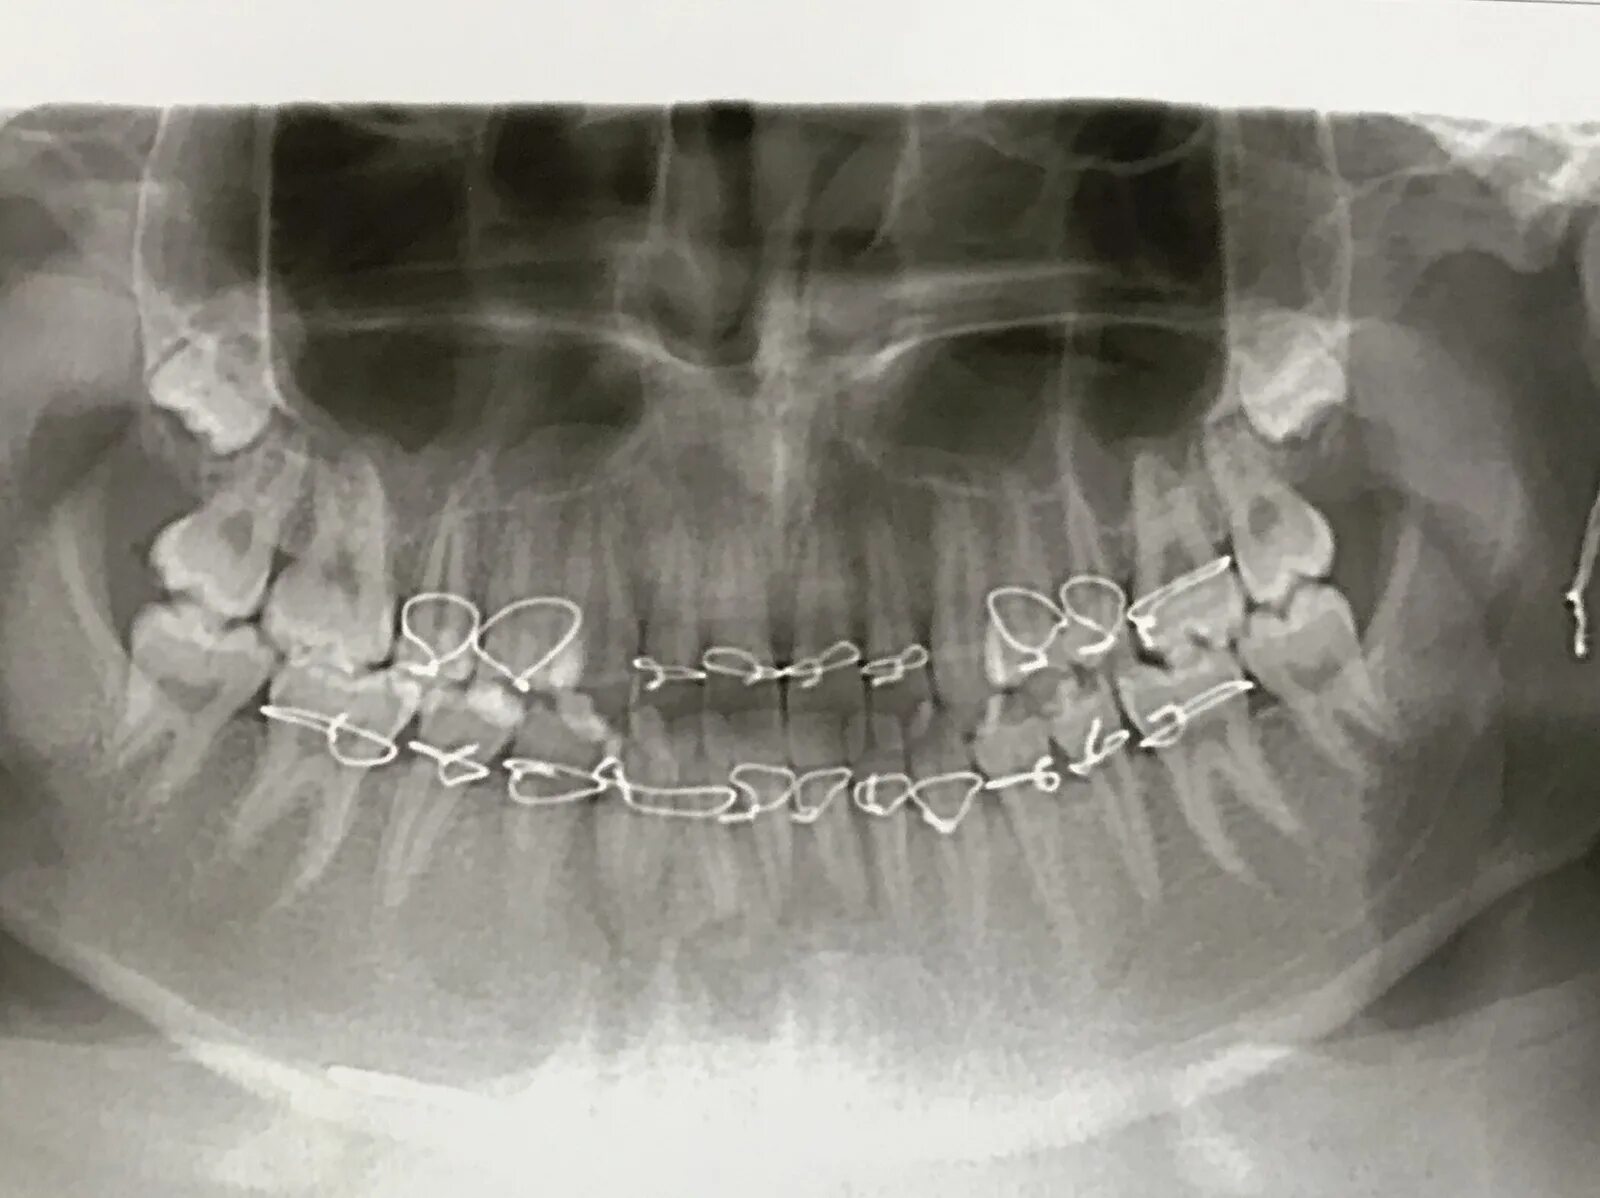

Переломы челюстей студфайл